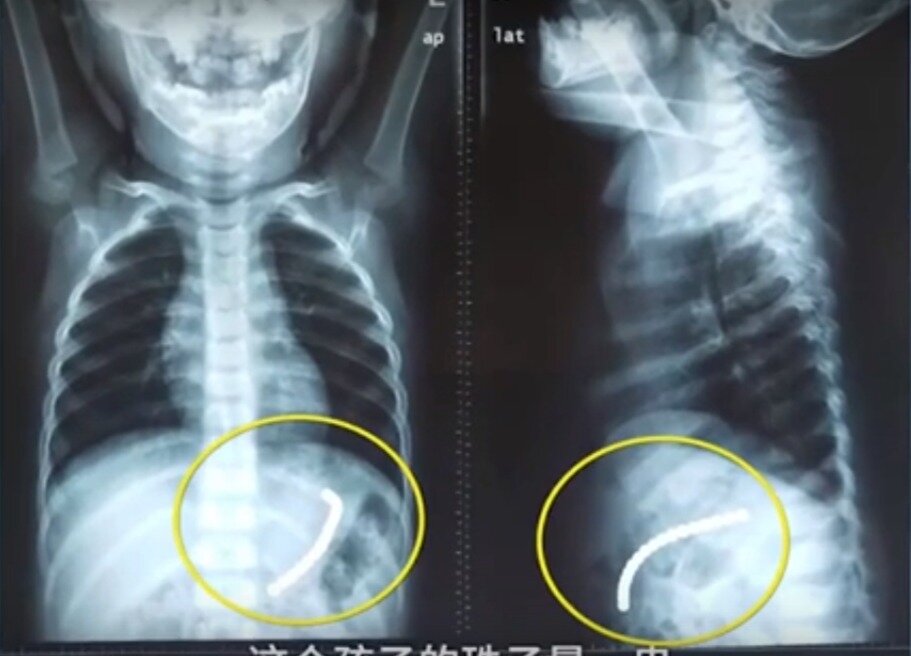

Хирурги из Китая извлекли из живота ребенка целый магнитный браслет. Оказалось, девочка проглотила 18 бусин, которые внутри желудка собрались в браслет. Двухлетняя девочка из Китая попала в больницу, после того как мама застукала ее за баловством с магнитными бусами. По словам матери, ей показалось, что девочка просто держит бусинки во рту. Тогда она решила достать их самостоятельно. Открыв ребенку рот она поняла, что девочка все проглотила. В четверг 14 марта девочка поступила в районную больницу - сообщает Daily Mail. При осмотре ребенка, девочка не жаловалась на боли и тошноту. В целом она чувствовала себя нормально. Когда врачи сделали рентгеновский снимок брюшной полости, они увидели, что бусы склеились в виде браслета. Некоторые из бусин прикрепились друг к другу через стенки желудка, от чего возникли язвы. За 15 минут врачам удалось изъять браслет из живота девочки при помощи эндоскопа. Как заявил доктор Ли Жуйфэн, ребенку очень повезло, что бусины не пошли дальше в кишечник.

В четверг 14 марта девочка поступила в районную больницу - сообщает Daily Mail. При осмотре ребенка, девочка не жаловалась на боли и тошноту. В целом она чувствовала себя нормально. Когда врачи сделали рентгеновский снимок брюшной полости, они увидели, что бусы склеились в виде браслета. Некоторые из бусин прикрепились друг к другу через стенки желудка, от чего возникли язвы.

За 15 минут врачам удалось изъять браслет из живота девочки при помощи эндоскопа. Как заявил доктор Ли Жуйфэн, ребенку очень повезло, что бусины не пошли дальше в кишечник. В ином случае последствия были бы более серьезными. Также врач призвал родителей отказаться от приобретения подобных игрушек для маленьких детей. Сейчас здоровью ребенка ничего не угрожает.